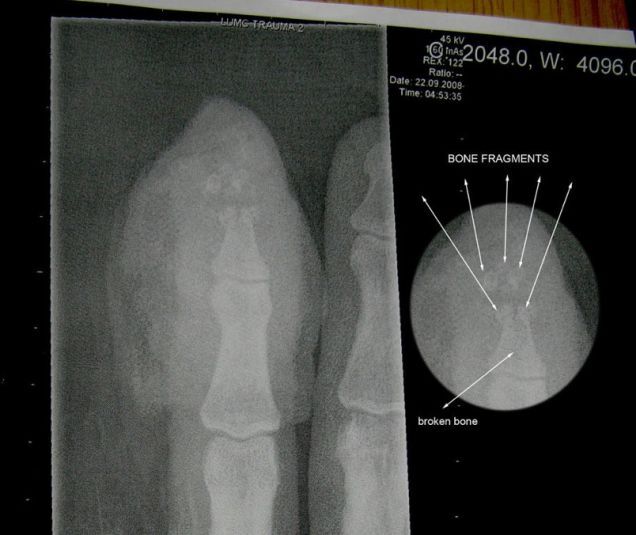

Dirk had an accident. Below is the X-ray showing his totally crushed finger tip. It took 1 1/2 hours of surgery to remove the shattered bones and repair the damage. Medically speaking, he crushed his right index finger distal phalange. The magnets had a 50 cm (20 inch) separation when they decided to fly together.